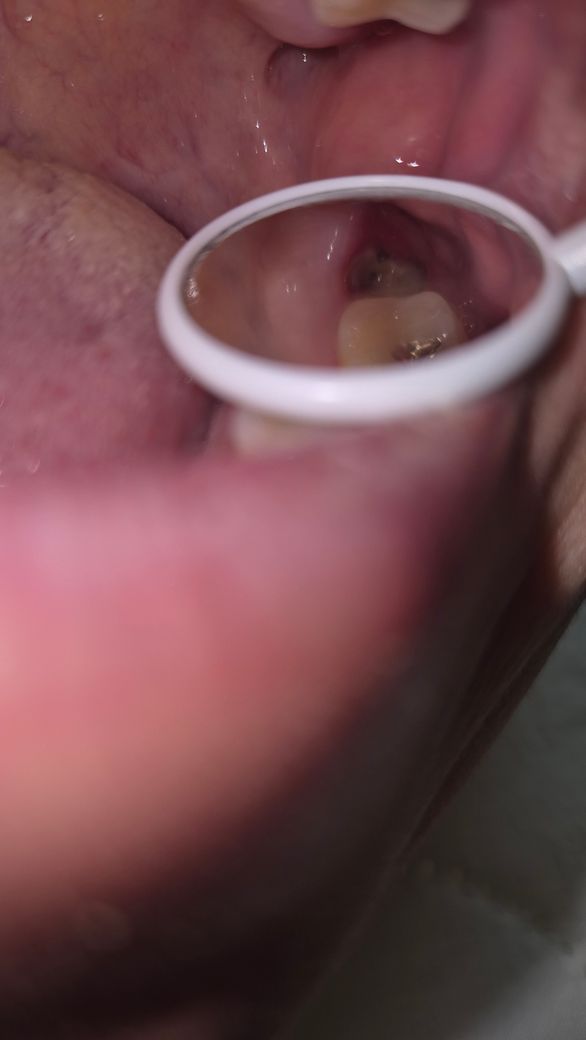

상악 어금니 발치후 노란덩어리 염증일까요?

상악 어금니발치하고 2주되었습니다.

치경으로 보니 구멍안에 저렇게 노란 덩어리가 생겼는데,염증 증상일까요??

• 2번 째 사진

정상적으로 아물고 있습니다. 잇몸 부위에 하얗게 딱지 앉은 것으로 보면 됩니다. 밑에서 살이 차올라 오면 없어집니다.